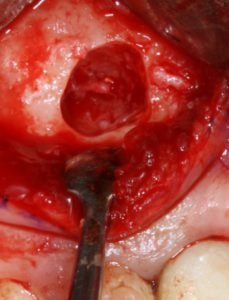

Figura 1: membrane do seio maxilar deslocada com área a ser enxertada pronta;